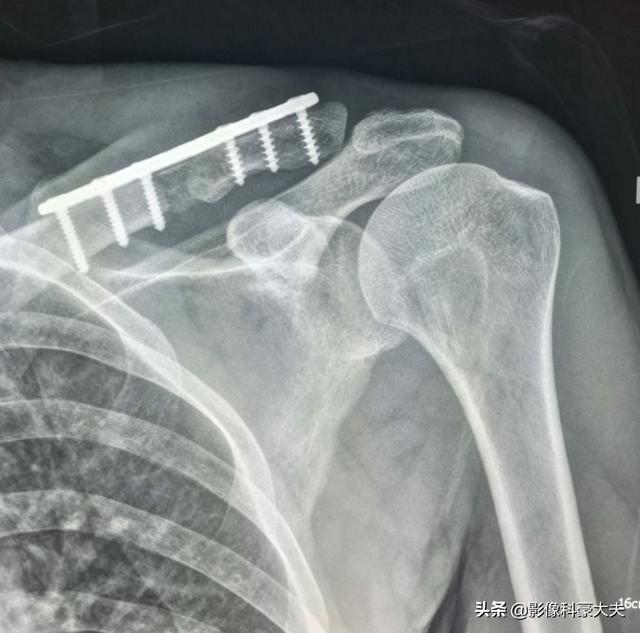

Il s'agit de l'opération de fixation interne qu'il avait réalisée à l'époque pour une fracture de la clavicule, une fracture pathologique qui a beaucoup de mal à guérir seule sans intervention chirurgicale.